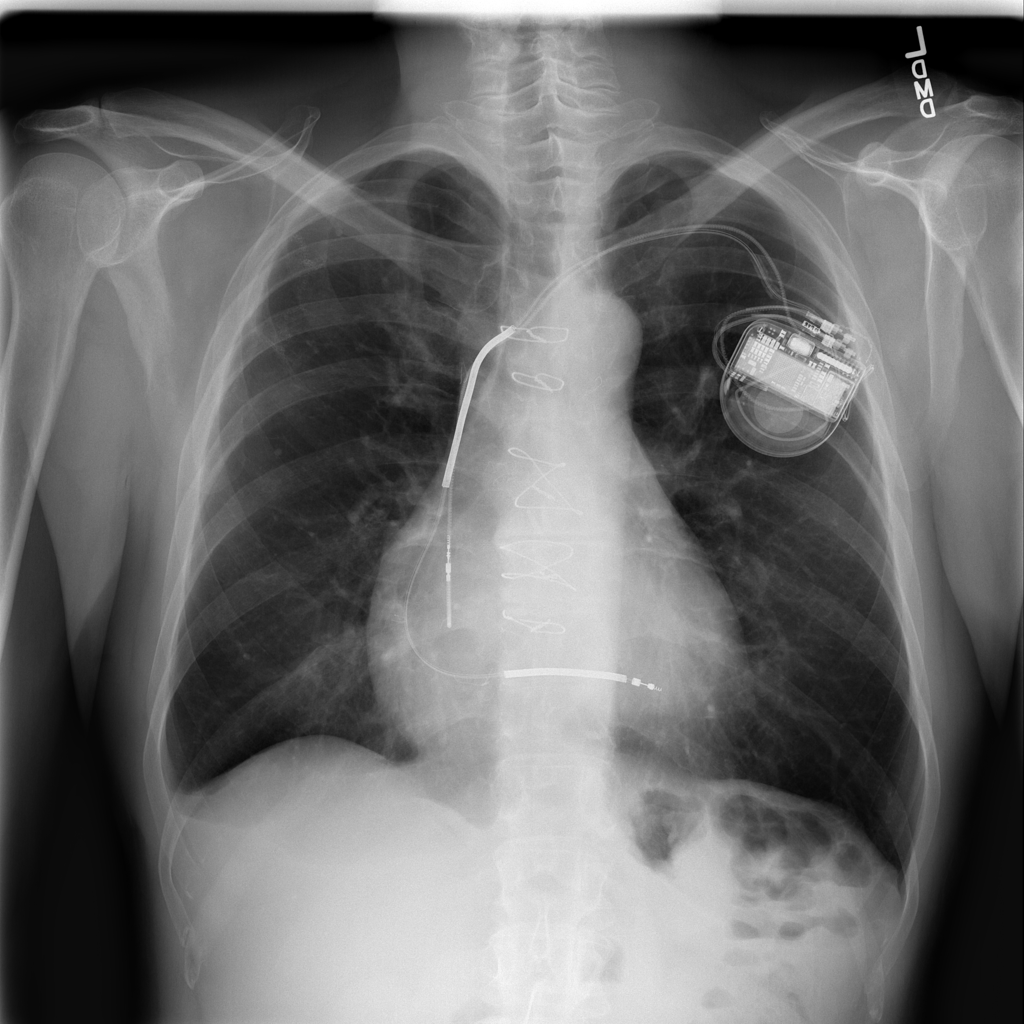

Cardiomegaly

Cardiomegaly means the heart appears enlarged on the chest X-ray. It is a descriptive imaging finding that can be related to heart strain, chronic pressure or volume changes, or even projection effects.

Showing up to 90 reference images for Cardiomegaly.

PAT-3384 · IMG-000Cardiomegaly

PAT-3384 · IMG-000

AP